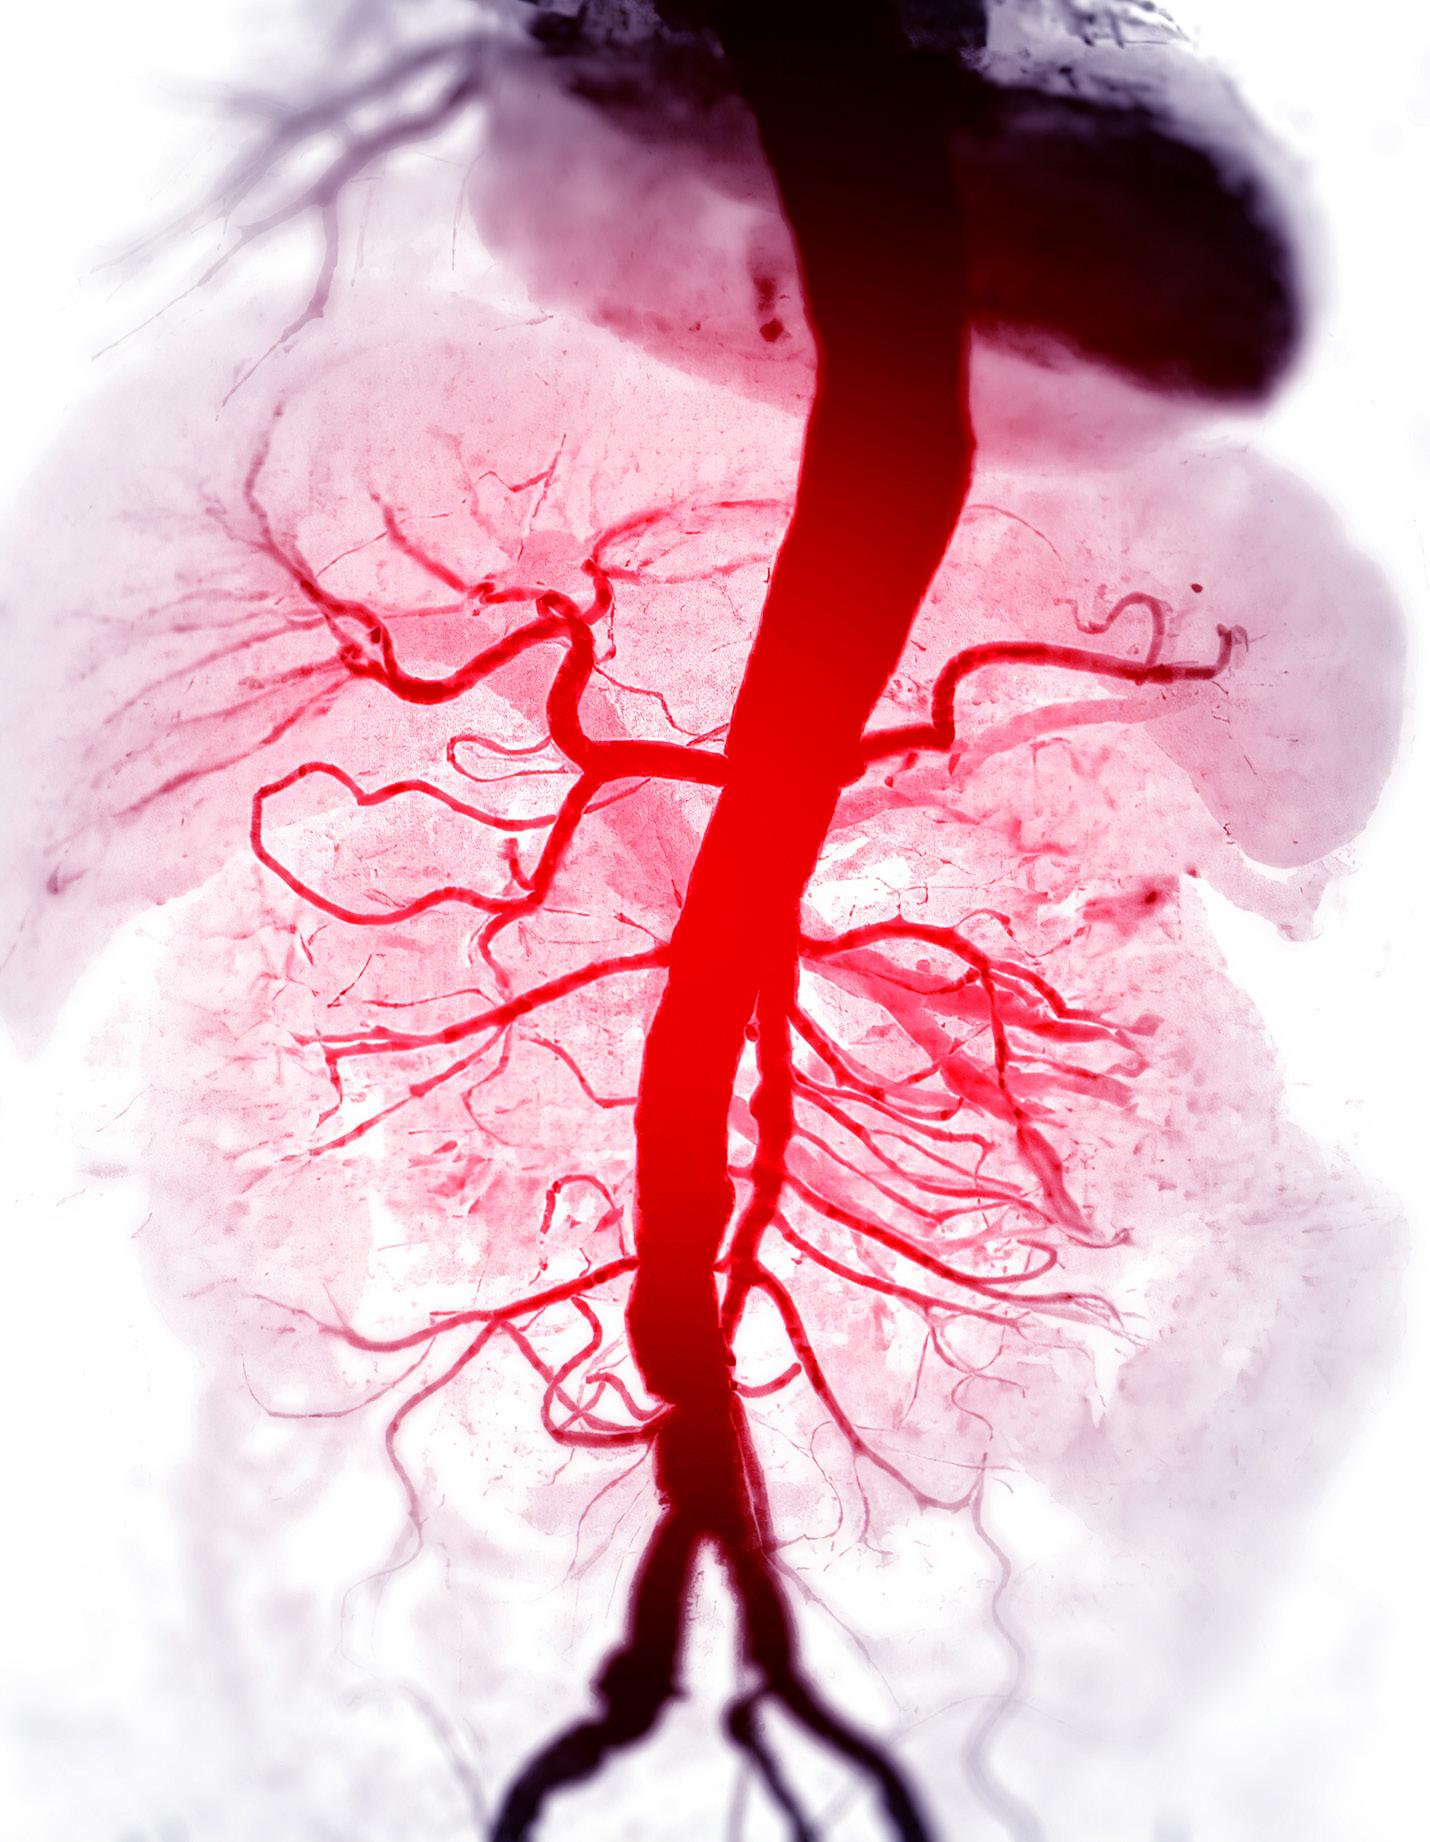

In the case covered in this article, an 85-year-old man with septic shock caused by a perforated sigmoid colon was profoundly hypovolemic and required crystalloid resuscitation and dual vasopressors. Ultrasound revealed that his internal jugular vessels were completely collapsible. Initial attempts to place the catheter were unsuccessful due to vessel collapse. The Trendelenburg position did not adequately dilate the internal jugular vein, as shown in Image 1. However, using a passive leg raise, significant dilation of the internal jugular vein was observed, enabling successful cannulation (Image 2).